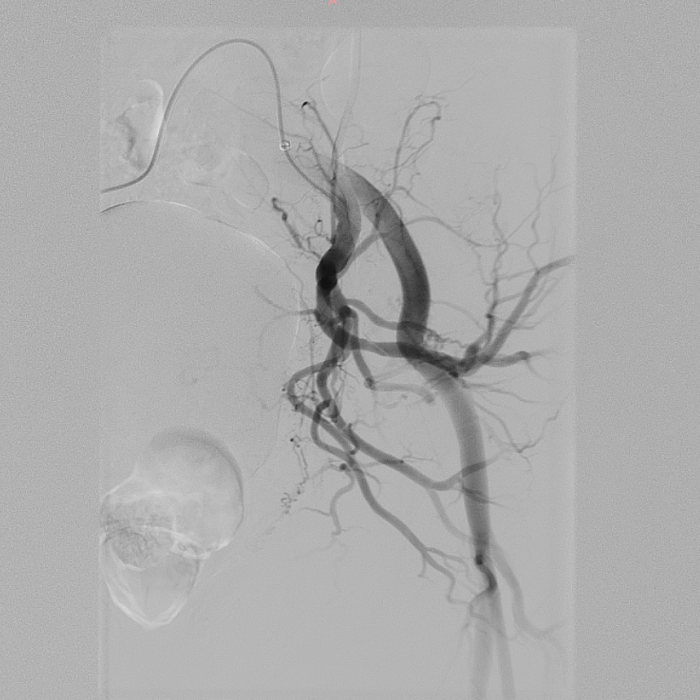

为了进一步探明真相、排除静脉外占位性病变,团队随即为患者安排了下肢CT血管造影(CTA)检查。检查结果一方面证实了患者左髂静脉受动脉压迫所致闭塞的事实;另一方面,一个关键性线索浮出了水面——影像上出现了左下肢静脉“早显”的现象,这通常强烈暗示动脉和静脉之间存在着异常沟通。

2 CTA可见左髂静脉受动脉压迫闭塞,同时左下肢静脉早显(1) 00_00_00-00_00_30.gif

血管造影影像显示患者左髂静脉受动脉压迫闭塞、左下肢静脉出现“早显”现象